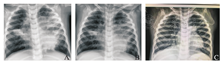

其中1例合并呼吸衰竭的患儿(男,1岁2个月),入院第2天出现呼吸急促,心率快,点头样呼吸,三凹征阳性,先后予鼻导管吸氧、高流量吸氧等,血氧均不能维持,遂予呼吸机辅助通气,痰培养回报肺炎链球菌,予头孢噻肟钠抗感染,甲泼尼龙抗炎,雾化吸痰,输注丙种球蛋白(2 g/kg)调节免疫、白蛋白(5 g)支持治疗;患儿入院时X线胸片提示两肺多发实变、肺不张(图2A),行纤维支气管镜检查及肺泡灌洗治疗,镜下见部分亚段痰栓堵塞,取出物呈塑形,肺泡灌洗液呼吸道病原提示甲型流感病毒阳性,治疗上加用帕拉米韦抗病毒,1周后复查胸片肺不张略吸收(图2B),但体温仍有反复,遂行第2次纤维支气管镜及肺泡灌洗治疗,镜下见黏膜充血、水肿,可见白黏痰;经上述治疗后,患儿体温平稳,呼吸血氧稳定,出院前复查X线胸片肺不张明显吸收(图2C)。本组治疗中所有患儿经治疗后均好转出院,出院前复查胸部影像学实变不张均较入院前不同程度吸收。出院后随访胸部CT有3例(7.3%)合并小气道病变。

A.入院时示两肺多发实变、肺不张;B.1周后复查示肺不张略吸收;C.出院前复查示肺不张明显吸收。